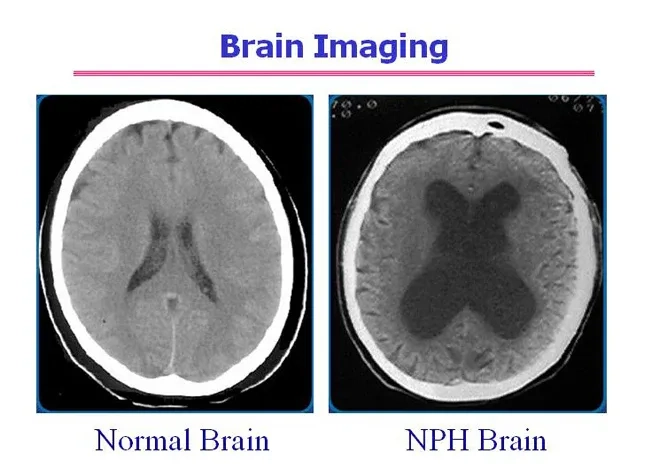

MRI brain scan showing enlarged ventricles in NPH

Understanding hydrocephalus in adults